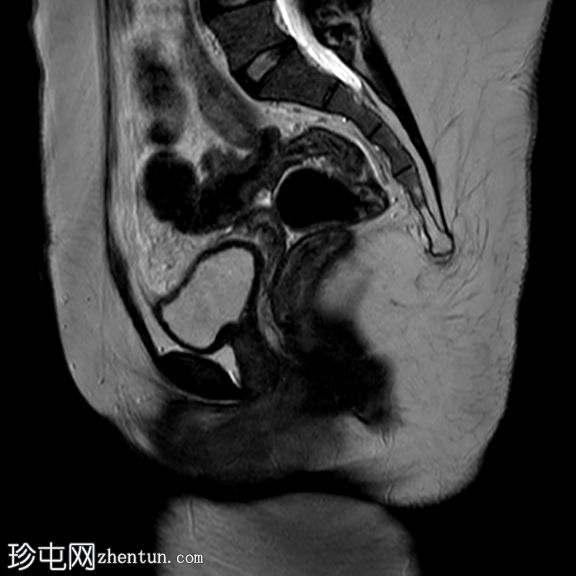

矢状位

T2加权像

盆腔两侧可见两个残角,位于双侧卵巢尾侧。可见一条水平带连接两个残角。左侧残角呈腔状,右侧残角呈非腔状。

可见宫颈阴道发育不全,从两个残角延伸出少量发育不良的宫颈组织带。

双侧卵巢功能正常,可见卵泡。

本病例展示了一种 Mayer-Rokitansky-Küster-Hauser 综合征 (MRKH),其特征为子宫缺失和双侧残角;左侧子宫角呈腔状,右侧子宫角呈非腔状。子宫角位于盆腔两侧,双侧卵巢尾侧,并由一条水平带连接。该病伴有宫颈阴道发育不全。